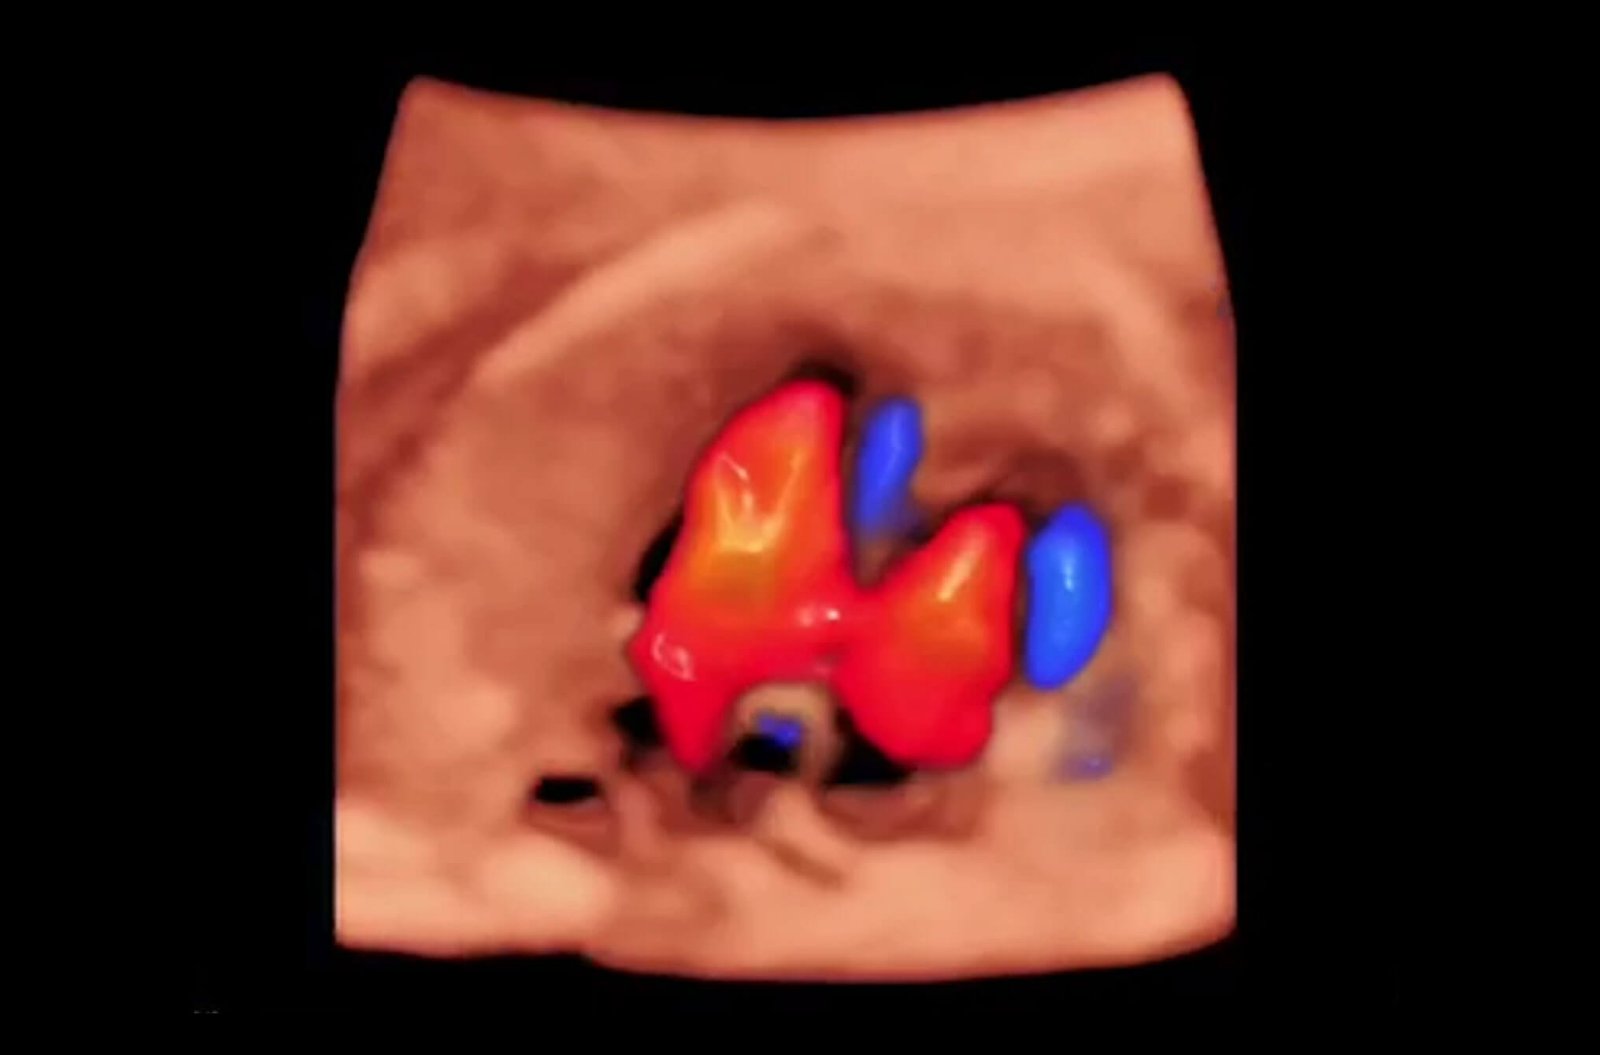

SR-Flow

Highly effective filter technology visualizes slow flows, enabling a vivid Doppler display with high sensitivity.

Micro F

Micro F provides an innovative method to expand the range of visible flow in ultrasound, especially for visualizing hemodynamic of tiny vessels.

Bright Flow

3D-like color Doppler flow strengthens boundary definition of vessel walls, without the need of using volume transducer.